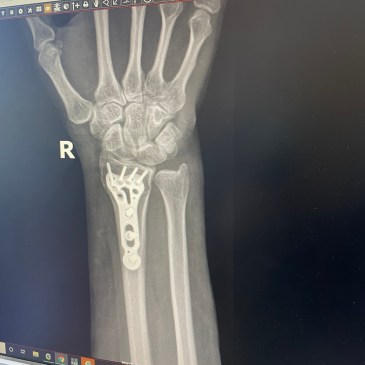

Better than all the Wrist

I’m punny. Well. Hello WordPress! I hope everyone is having a fantastic day. I am writing to you from the comfort of my kitchen. I had surgery yesterday morning and I wanted to tell you a little bit about it. I started off yesterday waking up at 5 AM, surgery was for 8AM and I … More Better than all the Wrist